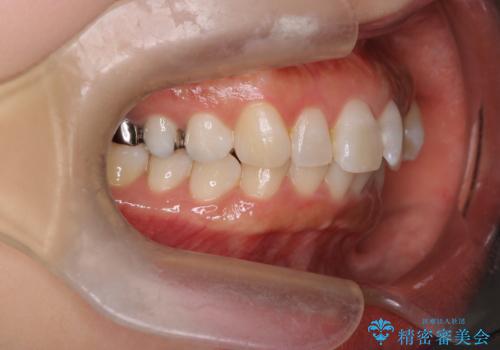

- 上下前歯のがたつきを主訴に来院されました。

口元も下げたいということもあり、上2本抜歯を行い治療を行いました。

抜歯を行い、前歯のがたつき、前歯の出ているところを改善できました。

患者様の満足感も高く治療を終えられました。